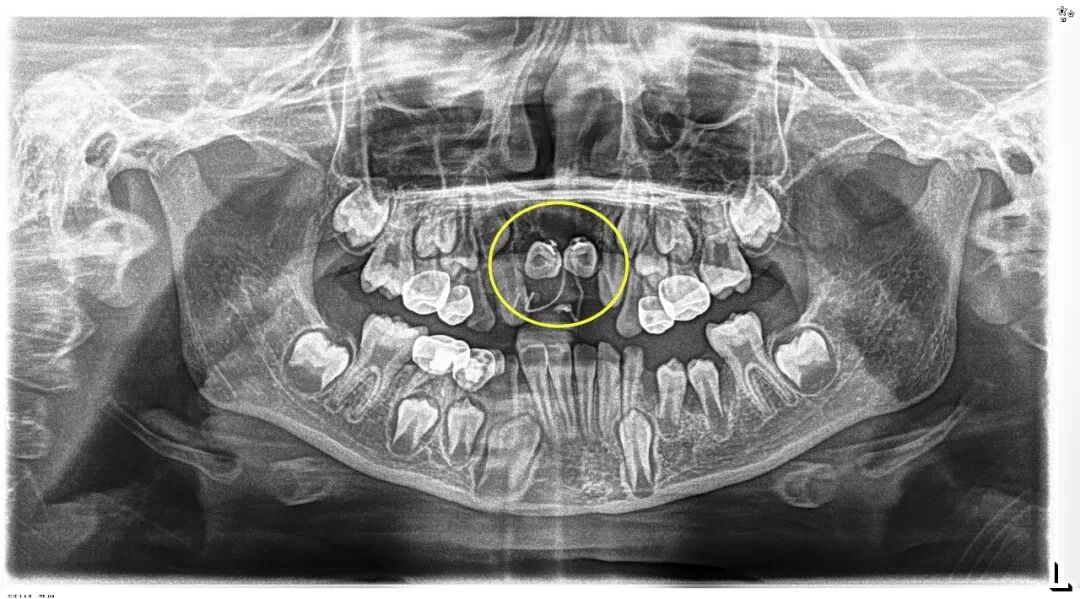

小胡已经9岁了,本该完成换牙的“新门牙”却迟迟没有萌出的迹象。家长带着他来到青岛市妇女儿童医院检查,拍摄X光片后发现,小胡的上颌骨内竟然埋伏着2颗多生牙,这两颗“不速之客”横着长在门牙牙根处,位置高至鼻底,还伴随唇向倾斜,阻碍了恒中切牙的正常萌出。

术后小胡恢复非常顺利。第一次复查时,两颗恒中切牙的舌侧扣和弹性附件的影像,下图可见: